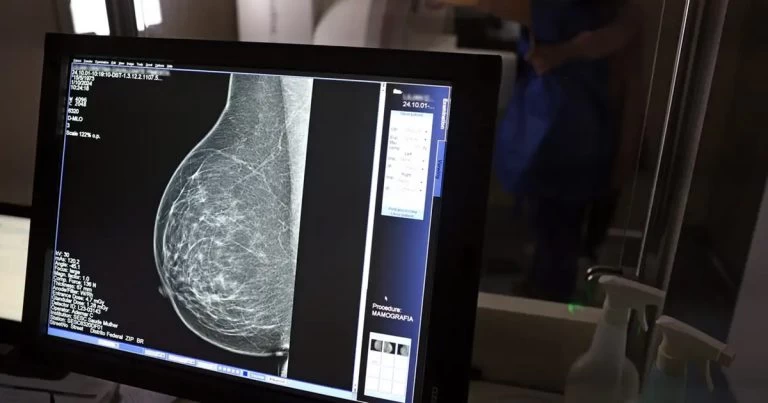

Tecnologia do micro-ondas propõe alternativa mais confortável e acessível à mamografia tradicional, mostra estudo

Um novo dispositivo para exames das mamas, que utiliza micro-ondas em vez de radiação ionizante, está sendo desenvolvido por pesquisadores da Escola Politécnica (Poli) da Universidade de São Paulo (USP) e do Instituto Federal de São Paulo (IFSP). Ainda em fase de protótipo, a tecnologia promete ser uma alternativa menos dolorosa e mais acessível à mamografia tradicional.